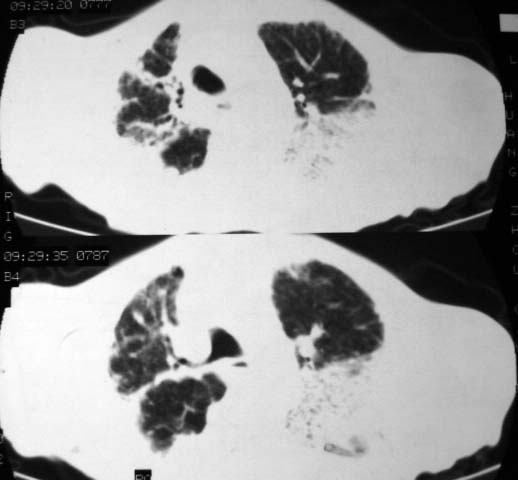

男,85岁,发热2月, 血常规:hgb99g/l.rbc2.55×1012/l.wbc3.8×109/l.n78.2%  l20.7% m1.1%.  hct26.3% .血沉20mm/hg.痰检结核杆菌阴性。ddp阳性。痰少粘稠色白。无咳血。

1.右上肺陈旧性肺结核灶;

2.左上肺、双下肺及右中叶肺炎(左上肺肺炎治疗后好转)

双肺结核

右上肺陈旧性肺结核灶,双肺感染灶〔大部份纤维化〕,肺气肿.

两肺陈旧性tb

双肺继发型结核

双肺继发型肺结核,肺纤维化,肺气肿,胸膜肥厚黏连。